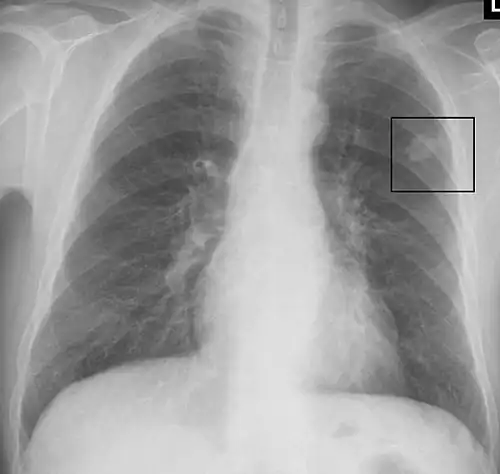

Chest X-ray showing lung cancer in the left lung

Most cancers are initially recognized either because of the appearance of signs or symptoms or through screening.[125] Neither of these leads to a definitive diagnosis, which requires the examination of a tissue sample by a pathologist.[126] People with suspected cancer are investigated with medical tests. These commonly include blood tests, X-rays, (contrast) CT scans and endoscopy.